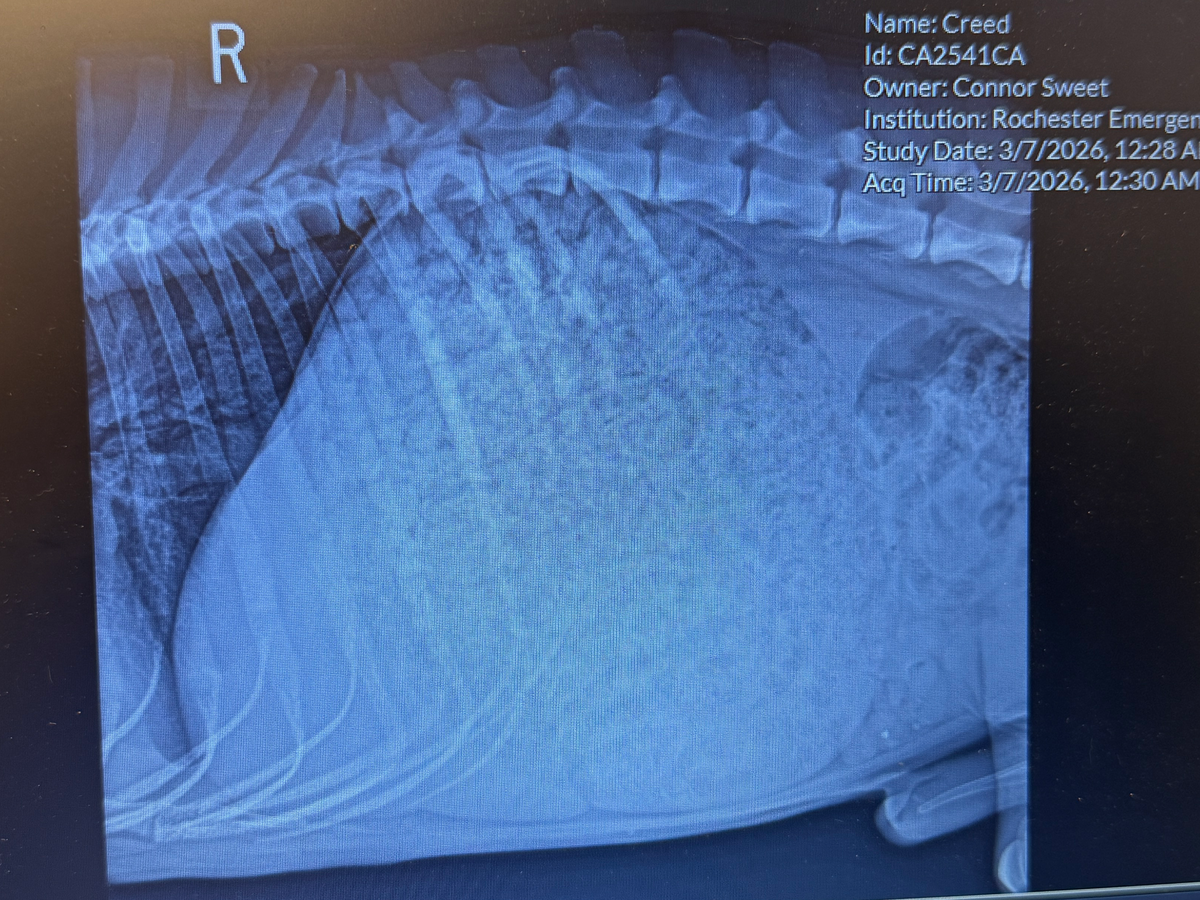

When we arrived around midnight, the emergency vet felt Creed’s lower stomach and immediately took him to the back room. He received a series of x-rays and an initial examination. To help him stay calm and comfortable, Creed had to be sedated and was given IV fluids. Creeds stomach was 3x the size of a normal stomach, for a deep chested GSD. His stomach was so large it was pushing his other organs together. He’s currently recovering overnight at the vet.